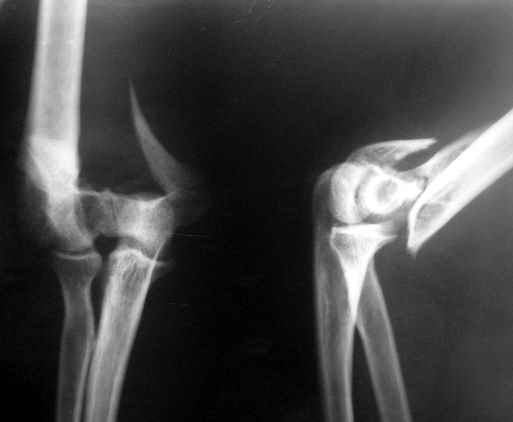

The recent x rays show established Non union with poor quality bone in the distal fragement. The joint is also appearing degenerate. In view of the multiple failed reconstructive surgeries, an Elbow replacement would seem reasonable.

Obviously there is no elbow joint...the options are few: (from the worst to the "best"...if any)

3. Total elbow replacement (semi constrained - as no ligaments to stabilize the joint) - Coonrad-Morrey, Discovery - Biomet - considering his age there is limited indication for that procedure.